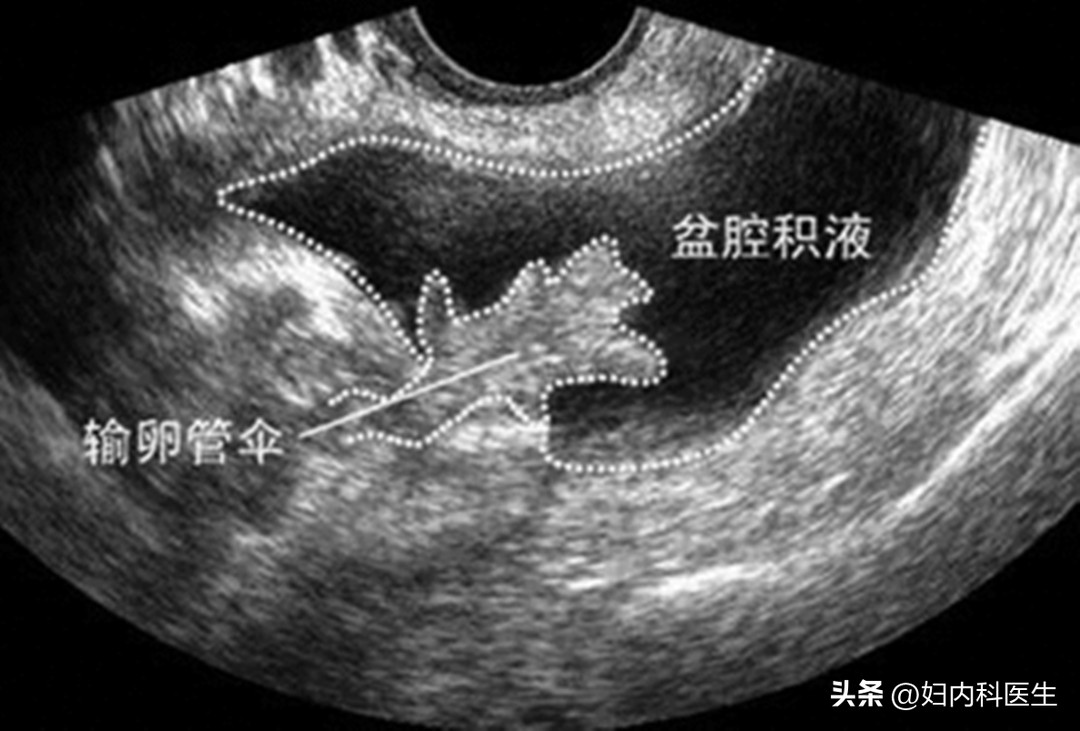

B超检查,正常的盆腔积液显示数据一般不会超过10毫米,也就是说检查显示液体暗区小于10毫米就是生理性积液,是一种生理现象,不必担心也不用特殊治疗,这种生理性现象的积液一般在一段时间后会自行恢复正常的。

病理性盆腔积液 ,在检查中显示积液区超过10毫米,而且范围较大,超声波投身也比较差,及提示是病理性盆腔积液了。